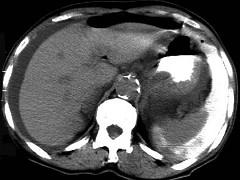

问题 男,44岁,突然中上腹痛,压痛,反跳痛,腹肌紧张,发热,白细胞计数升高,CT检查如图,最可能诊断是 ( )

选项 A、胰腺癌 B、胃癌 C、慢性胰腺炎 D、胃小弯溃疡穿孔 E、急性胰腺炎

答案 D